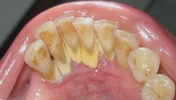

تسوس الأسنان

نزيف اللثة

أمراض الأسنان واللثة